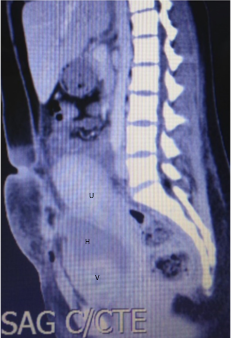

Al cuarto día postparto la paciente relata dolor en FII sin alteraciones en el transito urinario o digestivo. Al examen febril 38,5 ºC. Abdomen: blando, depresible, se palpa tumoración dolorosa en FII sin elementos de irritación peritoneal. El hemograma presenta glóbulos rojos 3.56mill/µL, hemoglobina de10.2 g/dL, hematocrito 31.9 %, 20.3mil/µL glóbulos blancos, plaquetas 384000/mL. Proteína C reactiva 91 mg/L.Función renal, hepática y crasis normales. Se solicita ecografía transvaginal que informa: Útero de 156 mm de longitud por 72 mm transverso y 85 mm antero posterior. En cara posterior izquierda una imagen heterogénea de 99 mm por 51mm, compatible con hematoma. Para valorar extensión del mismo se complementa con resonancia magnética (RM) abdomino pélvica que informa: útero aumentado de tamaño de 193 mm diámetro longitudinal sin imágenes patológicas en cavidad uterina. Colección en pelvis menor, a nivel de fosa ilíaca izquierda de 138mm longitud por 70 mm transverso por 68 mm antero posterior sin realce con contraste y en continuidad con ésta dos imágenes, una pararectal izquierda de 70mm de longitud por 33mm transverso y 66 mm anteroposterior, la otra en espacio pararectal derecho de 48mm de longitud por 28mm transverso y 70mm anteroposterior. (Figura I y II). En suma: hematomas subagudos subperitoneales en FII y a ambos lados del recto. Ante la evolución desfavorable y con planteo de hematoma del ligamento ancho complicado por proceso infeccioso se opta por laparotomía exploratoria y terapéutica. En el intraoperatorio se visualizan múltiples hematomas subperitoneales y en el ligamento ancho izquierdo que se evacúan, no sangrado activo, se realiza lavado del lecho y se coloca drenaje por contra abertura. (Figura III). La paciente se retira estable del block quirúrgico, se instaura nuevo plan antibiótico en base a Imipenem 500mg cada 6 hs i/v. Evoluciona favorablemente sin dolor ni síndrome toxoinfeccioso, no alteración en los tránsitos, genitorragia escasa. A los 30 días se otorga alta con tomografía computada de abdomen y pelvis que evidencia reducción de colecciones mayor al 50%. Seguimiento en primer nivel de atención clínico e imagenológico con alta a los 60 días posparto con resolución total de colecciones.

Figura I. RM. Hematoma de ligamento ancho: colección en fosa ilíaca izquierda (flecha 1 - F1), para rectal derecha (flecha 2- F2) e izquierda (flecha 3- F3).